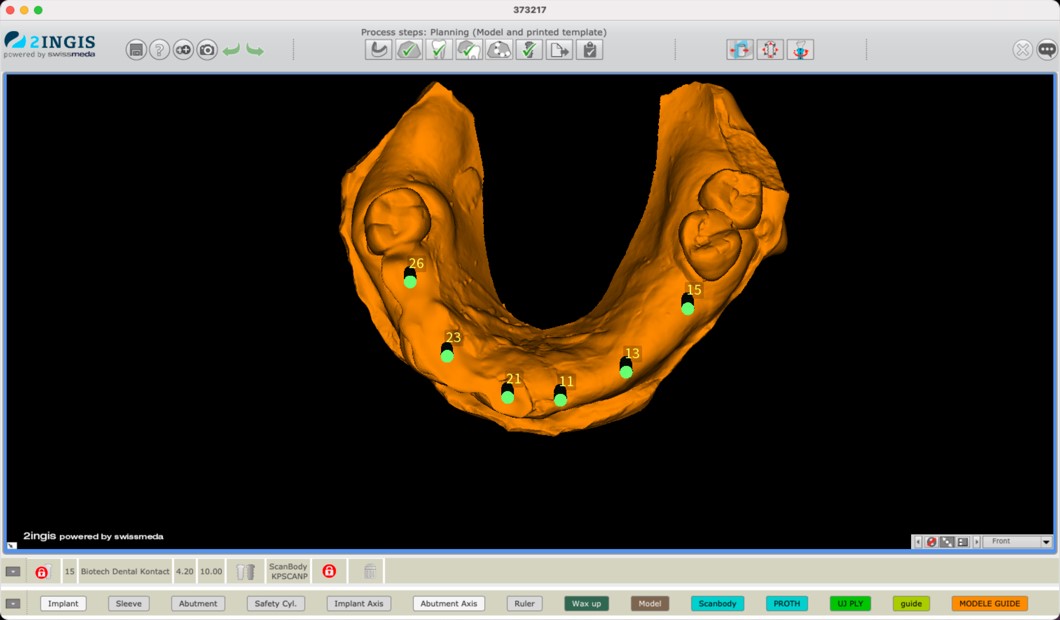

Prima dell’intervento, il posizionamento degli impianti veniva attentamente pianificato utilizzando il software SMOP® (Fig. 2 a) e la guida aperta TwinGuide® che era progettata di conseguenza (Fig. 2 b,c).

Pianificazione del caso

Fig. 2(a)

Preparazione del caso 2

Fig. 2(b)

Preparazione del caso 3

Fig. 2(c) Pianificazione del caso all’interno di software per la chirurgia guidata.